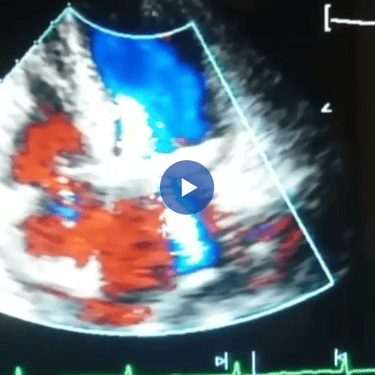

El Ecocardiograma ofrece imágenes del corazón en movimiento y tiempo real.

Mediante ultrasonido, la ecocardiografía aporta información acerca de:

Funcionamiento de las válvulas cardiacas.